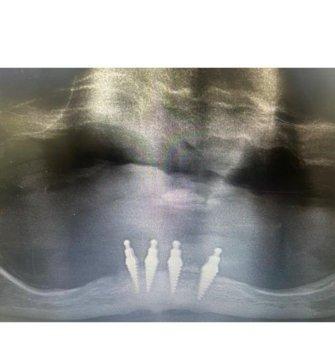

• in House 3d scan • outstanding reviews

• same day impLants and teetH

• aLL aspects oF impLant surgery,

• make a Free 45 minute consuLtation appointment today

ARE ThEY TOO lOOSE TO kEEp ThEM IN AND ARE YOU UNABlE TO EAT wITh ThEM? HAvE YOU CONSIDERED DENTAl IMplANTS? WE CAN OffER IMMEDIATE IMplANTS wITh SAME DAY STABIlISATION TO TRANSfER YOUR lOOSE DENTURE INTO A SECURE STABlE DENTURE ThAT YOU wIll BE ABlE TO EAT ON ThE SAME DAY.